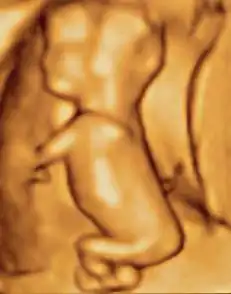

A human fetus, attached to placenta, at three months gestational age

In humans, the fetal stage starts nine weeks after fertilization.[11] At this time the fetus is typically about 30 millimetres (1+14 in) in length from crown to rump, and weighs about 8 grams.[11] The head makes up nearly half of the size of the fetus.[12] Breathing-like movements of the fetus are necessary for the stimulation of lung development, rather than for obtaining oxygen.[13] The heart, hands, feet, brain, and other organs are present, but are only at the beginning of development and have minimal operation.[14][15] Uncontrolled movements and twitches occur as muscles, the brain, and pathways begin to develop.[16]